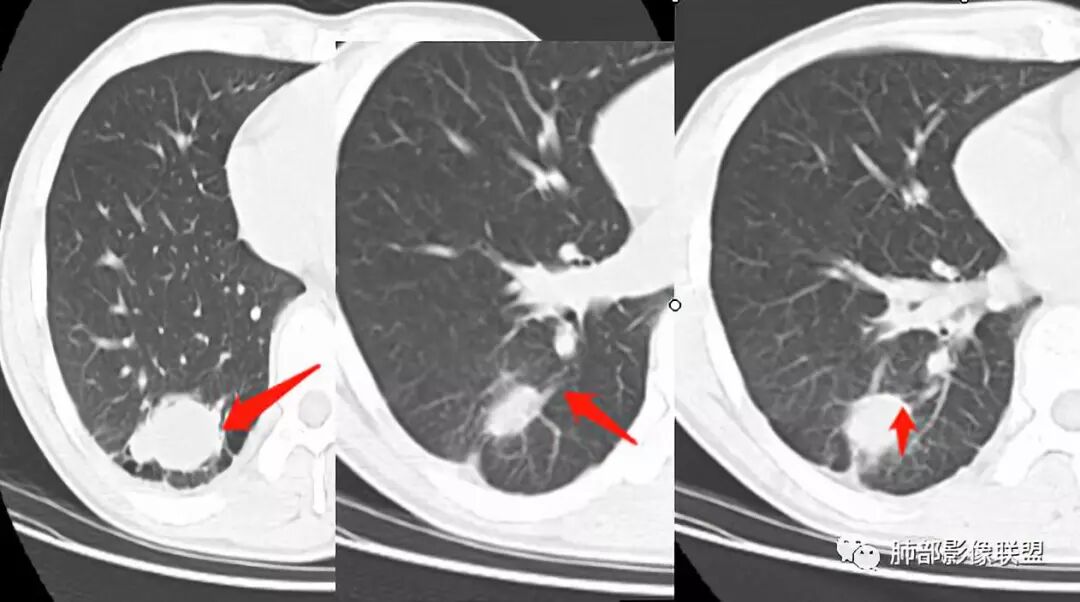

右肺下叶囊性病变,边缘光滑,薄环状强化,内壁较光滑

血管贴边

周围多发长索条

远端有斑片状条带状高密度影,周围肺气肿

附近胸膜增厚,内有血管影

第一,看支气管,有一条支气管从病变边缘走过,有一条支气管在病灶近端堵塞;说明病变和支气管有关系,一般情况下支气管堵塞应该考虑炎性病变或恶性肿瘤才可以符合,不符合良性肿瘤,当然肺囊肿也可以,因为它是先天发育变异的。

第二,看强化幅度,内无强化,但是我担心图像并不够薄,目测观察有所偏差,但是现可见薄壁样强化;从这个角度考虑,良性肿瘤就不符合了,如PSP就不太支持了,这个病变远端有分叶、有小尾巴,周围有索条状影,除非PSP合并感染,二元论,否则单纯PSP周围不会有这种表现。

第三,病变旁边胸膜区域有增厚,似乎有些血管增粗,虽然这不是隔离征好发区域;它应该偏内侧一点,但是我们应该最好有重建血管先排除隔离征;从所给图片看,病灶具体走形外面没有看见血管进入,因为是囊性病变嘛。